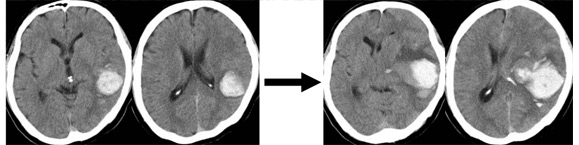

下記示します頭部CTは発症時の血圧管理が不十分だったものです。発症時に比較して3時間後のCTでは血腫が明らかに増大しているのがよくわかります。発症時の血圧管理は非常に大事です。